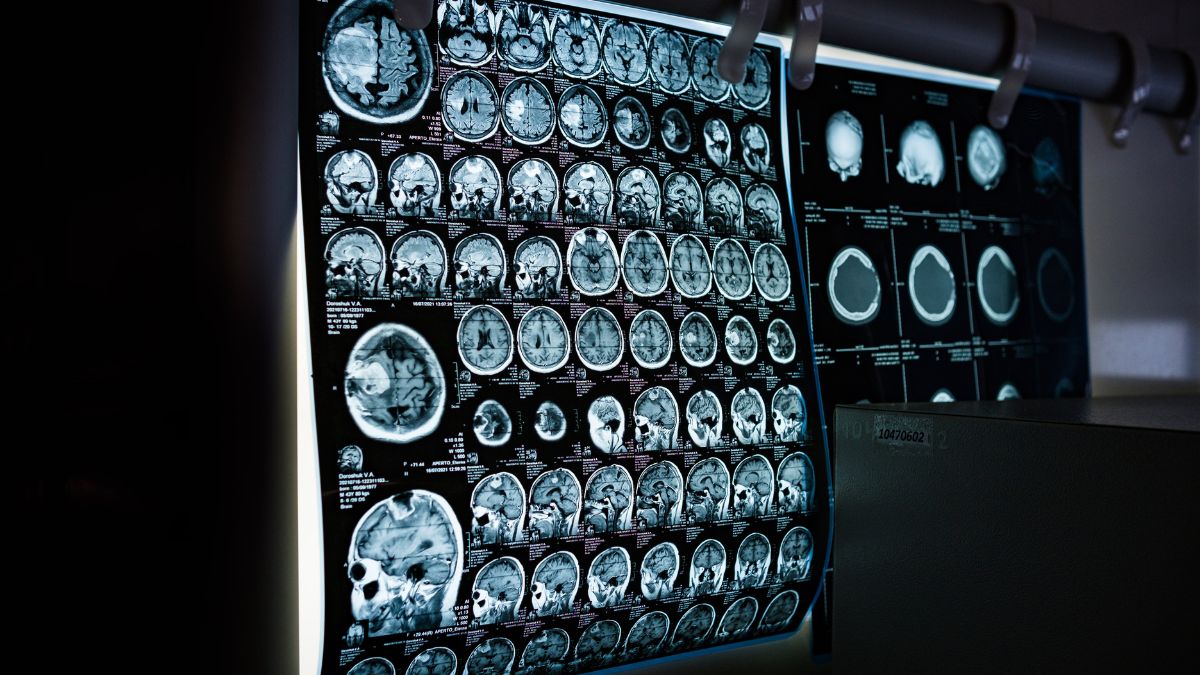

Un creier înghețat care funcționează din nou? Oamenii de știință din Germania au făcut o descoperire uriașă, restabilind activitatea în țesutul cerebral după o răcire extremă. Această descoperire ar putea deschide posibilități complet noi în medicină și în salvarea de vieți. Timp de ani de zile, crioprezervarea a fost asociată mai ales cu filmele science-fiction. Ideea înghețării oamenilor pentru a-i „trezi” în viitor părea nerealistă.

Cea mai mare problemă nu era însă procesul de răcire în sine, ci ceea ce se întâmpla cu țesutul – mai ales cu creierul. În timpul înghețării, apa formează cristale de gheață care distrug structurile celulare delicate. În cazul creierului, asta înseamnă distrugerea neuronilor și a conexiunilor responsabile de memorie și conștiință. Până acum, asta însemna un singur lucru: după dezghețare, țesutul nu era capabil să funcționeze.

O echipă de cercetători din Germania a folosit o tehnică numită vitrificare, care permite evitarea acestei probleme. Țesutul este răcit atât de rapid încât apa nu apucă să formeze cristale de gheață. În schimb, capătă o formă asemănătoare sticlei. În această stare, toate procesele biologice sunt oprite, dar structura celulelor rămâne intactă. Aceasta este diferența-cheie care a făcut posibilă realizarea acestui progres.

Cercetătorii au efectuat un experiment pe fragmente de creier de șoarece, mai exact din hipocamp – zona responsabilă de memorie și învățare. Țesuturile au fost înghețate la -196°C și păstrate chiar și timp de o săptămână. După dezghețare, s-a constatat că: